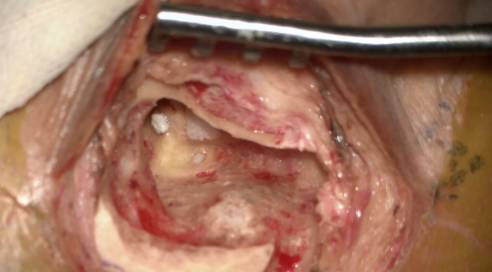

图片 1.png

半规管阻塞